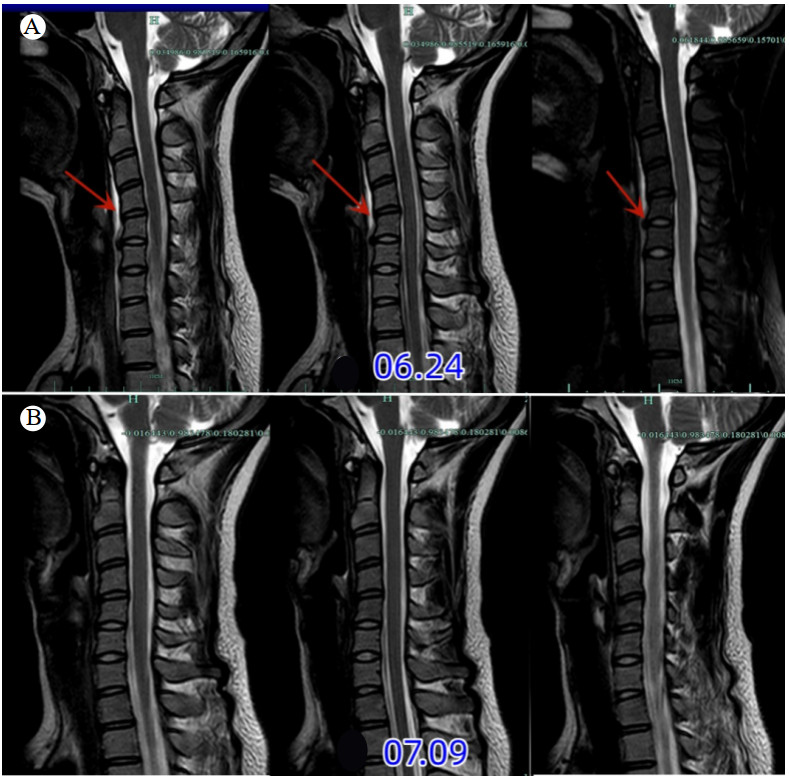

1 病例资料患者,女性,28岁,信息技术程序员,因“颈痛1 d”于6月23日到杭州市中医院就诊。患者自诉1 d前无明显诱因出现颈部疼痛,呈持续性,伴轻度咽部疼痛,无发热、咳嗽,至本院急诊就诊。患者既往有颈痛病史,影像检查见图 1。急诊给予血常规(白细胞、C-反应蛋白均正常)和颈椎CT检查(见图 2A)提示颈椎退变,曲度变直,C5/6前缘骨赘。初步诊断考虑“颈痛,颈肌扭伤”,给予洛索洛芬钠片口服治疗。6月24日患者颈部疼痛明显加剧,无法吞咽食物(吞咽困难),于五官科门诊行喉镜检查未见明显异常,于消化内科门诊就诊,考虑颈痛明显建议先于骨科就诊,未进一步行胃镜等相关检查。颈椎MRI(见图 3A)提示:颈椎椎前水肿积液,考虑“急性钙化性肌腱炎”,给予糖皮质激素(氢化泼尼松龙)、林格氏液静滴,患者自诉颈痛及吞咽困难/疼痛有所好转。6月24~26日连续静脉应用糖皮质激素3 d,患者颈部疼痛及吞咽疼痛明显缓解,改用洛索洛芬钠片继续治疗1周。7月8日于骨科门诊复查颈椎X线(图 2B)提示颈5/6前缘钙化明显缩小(较6月24日),MRI(图 3B)提示颈椎前缘水肿信号消失,颈椎退变。

| 注:A为颈椎曲度变直,颈椎椎前水肿积液;B为颈椎曲度变直,颈椎椎前水肿积液消失 图 3 患者发病时及治疗后颈椎椎前水肿MRI变化 |

ACTLC涉及到急诊科、骨科、神经科、五官科、消化科等学科,临床医生对此疾病认识不足及病程的良性自限性是漏诊的最主要原因。在本病例报告中,患者以“颈痛”为首发症状,初步诊断为“落枕、颈肌扭伤”,反复追问病史,患者诉“伴有咽部不适感”,在前期ACTLC的诊疗经验基础上,给予颈椎CT检查(图 2)提示颈5/6前缘钙化/骨化影,不符合典型的ACTLC,故加做MRI。病程的第2天,患者颈部疼痛明显加重,伴吞咽疼痛、吞咽困难、无法进食,MRI(6月24日)显示颈椎前缘条状水肿影,波及C3-T1节段,未出现典型的咽后壁积液,五官科喉镜检查正常。结合患者临床症状及辅助检查结果,诊断为“急性钙化性颈长肌肌腱炎(非典型部位)”,给予静脉应用糖皮质激素治疗,患者症状明显缓解,在病程的第7天,患者症状完全消失,第10天复查X线显示颈椎前缘钙化影明显缩小,MRI显示颈椎前缘水肿完全消失,验证了“钙化的自发性吸收理论”。

钙化性肌腱炎的自然病程通常分为三期:钙化前期、钙化期、钙化后期;钙化期又分为钙化形成期、静止期和重吸收期[9]。在钙化的吸收阶段,钙化沉积物被炎性细胞吞噬,诱发炎症反应,这是患者最痛苦的阶段[9]。Tezuka等[10]回顾文献总结17例ACTLC患者钙化物影像学吸收现象,发现吸收时间分别为 < 1个月(11例)、1~2个月(4例)、> 2个月(2例);且临床症状并不完全与影像学表现相一致,临床症状的完全恢复需要1~2个月,钙化物的完全消失通常需要3~4周。本病例图 1A显示C5/6前缘未见骨化,属于钙化前期;而图 1B显示钙化,而无相应的临床症状,属于钙化期;图 2A出现典型的临床症状,属于吸收期;在末次随访时,C5/6前缘钙化影几乎完全消失,属于钙化后期。ACTLC为良性自限性疾病,疼痛多在1周达到高峰,2~4周缓解[11]。本病例经过糖皮质激素的治疗,病程持续1周即完全缓解,对ACTLC充分认识的基础上早期应用糖皮质激素能够大大缩短病程,减轻患者痛苦。